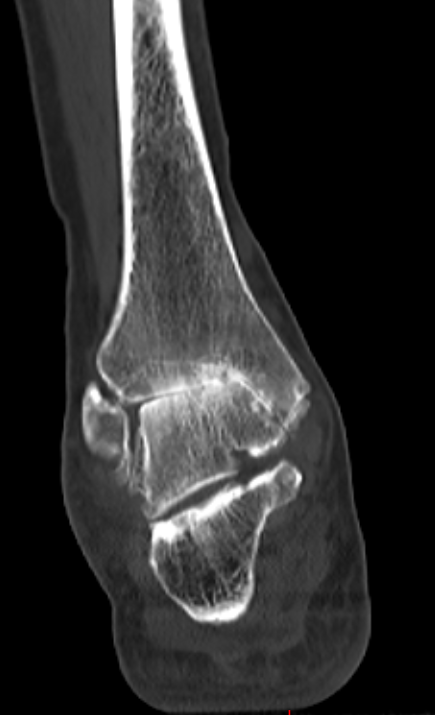

第一台手术的患者是位75岁的叔叔,被“脚脖子”痛缠了4年,疼得越来越厉害,病情已经到了严重阶段。

术前踝关节CT

武勇主任团队给他做了3D打印导板辅助下人工全踝关节置换术。

这种手术适合踝关节病严重的患者,通过替换病变的关节结构,能帮着缓解疼痛、恢复关节活动,让老人日常走路更自在些。